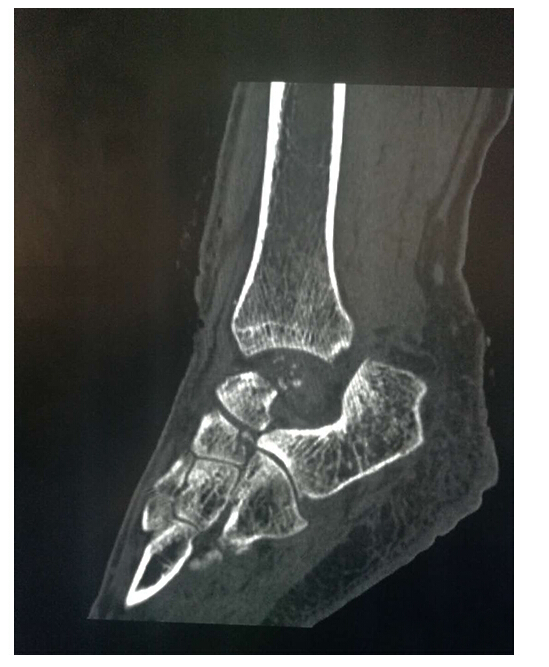

患者女,43歲。不幸遭遇車禍致左踝關(guān)節(jié)開放性脫位并距骨體缺損收住院急診手術(shù),手術(shù)過程中發(fā)現(xiàn)距骨粉碎性骨折,距骨體缺失。這種病例在以往只能從身體其他部位取骨填充該處缺損進(jìn)行踝關(guān)節(jié)融合,這樣患者將喪失踝關(guān)節(jié)的功能,給行走帶來不便。

此次手術(shù)植入的3D打印全距骨假體是西安高新醫(yī)院骨一科醫(yī)療團(tuán)隊(duì)根據(jù)患者的病情,利用患者自身踝關(guān)節(jié)CT數(shù)據(jù)建立患側(cè)與健側(cè)的三維數(shù)字模型,根據(jù)健側(cè)距骨數(shù)據(jù)鏡像出患側(cè)距骨三維模型。為患者“私人定制”量身定做距骨與人體完全匹配,完全個(gè)性化制作。材料使用彈性、硬度和柔韌性與人體相似的鈦合金材料,假體關(guān)節(jié)面以外采取粗糙面有很多微孔有利于骨長入、肌腱韌帶附著,維持了踝關(guān)節(jié)的穩(wěn)定。具有良好的應(yīng)用前景。